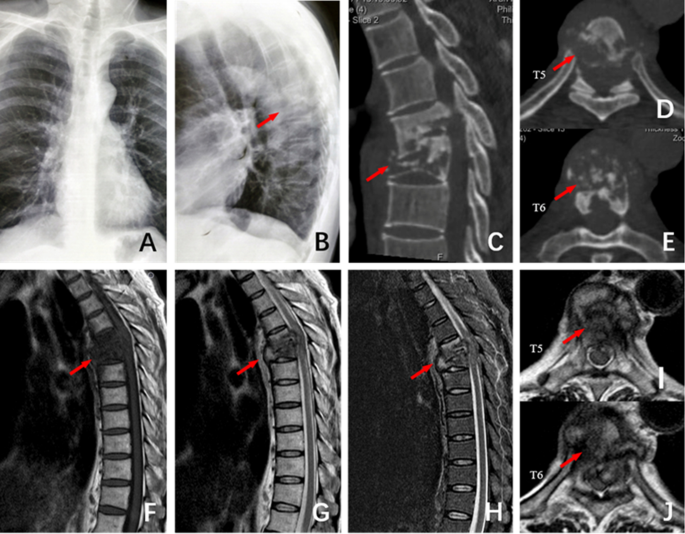

The patient, male, 51 years old, T5 ~ T6 spinal tuberculosis secondary to kyphosis deformity. (A) and (B) The frontal and lateral X-ray films before surgery showed vertebral destruction of T5 ~ T6 and Cobb Angle of 40°. (C–E) Preoperative CT showed severe damage to the anterior column of the T5 ~ T6 vertebral body and normal posterior column. (F–J): Preoperative MRI showed vertebral destruction of T5 ~ T6 and obvious compression of the spinal cord.